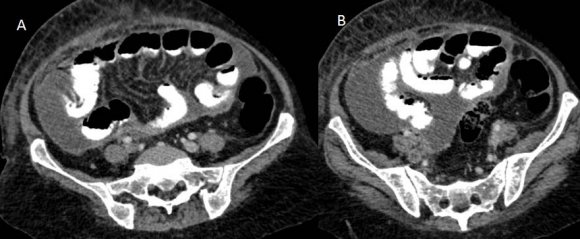

CT scan of the abdomen and pelvis (Figures: 4-8) showed changes of fatty infiltration in the liver. Multiple well-defined lymph nodes of size 1 to 2 cms were noted at portahepatis, peripancreatic region, celiac axis, left renal hilum, preaortic and para-aortic regions, precaval and paracaval regions and in right internal iliac region. Most of the lymph nodes showed peripheral enhancement with central hypodense areas of necrosis. A conglomerated matted lymph nodal mass of size 35 x 24 mm noted in the precaval region. Multiple ill-defined and nodular soft tissues infiltrate noted within the mesentery. Moderate ascites noted with mild peritoneal enhancement without septations. Ileo-caecal junction and other bowel loops appeared normal. IVC distal to renal veins showed persistent filling defect of size 10 (Anteroposterior) x 16 (Transverse) mm extending over a length of 67mm with peripheral enhancement in contrast study extending to right common iliac vein suggestive of IVC and right common iliac vein thrombosis.

Figure 7. Figure 7 :Figure 8 :

78Figure 7: Contrast-enhanced CT scan of the abdomen showing thrombosis in the right common iliac vein (A, B)